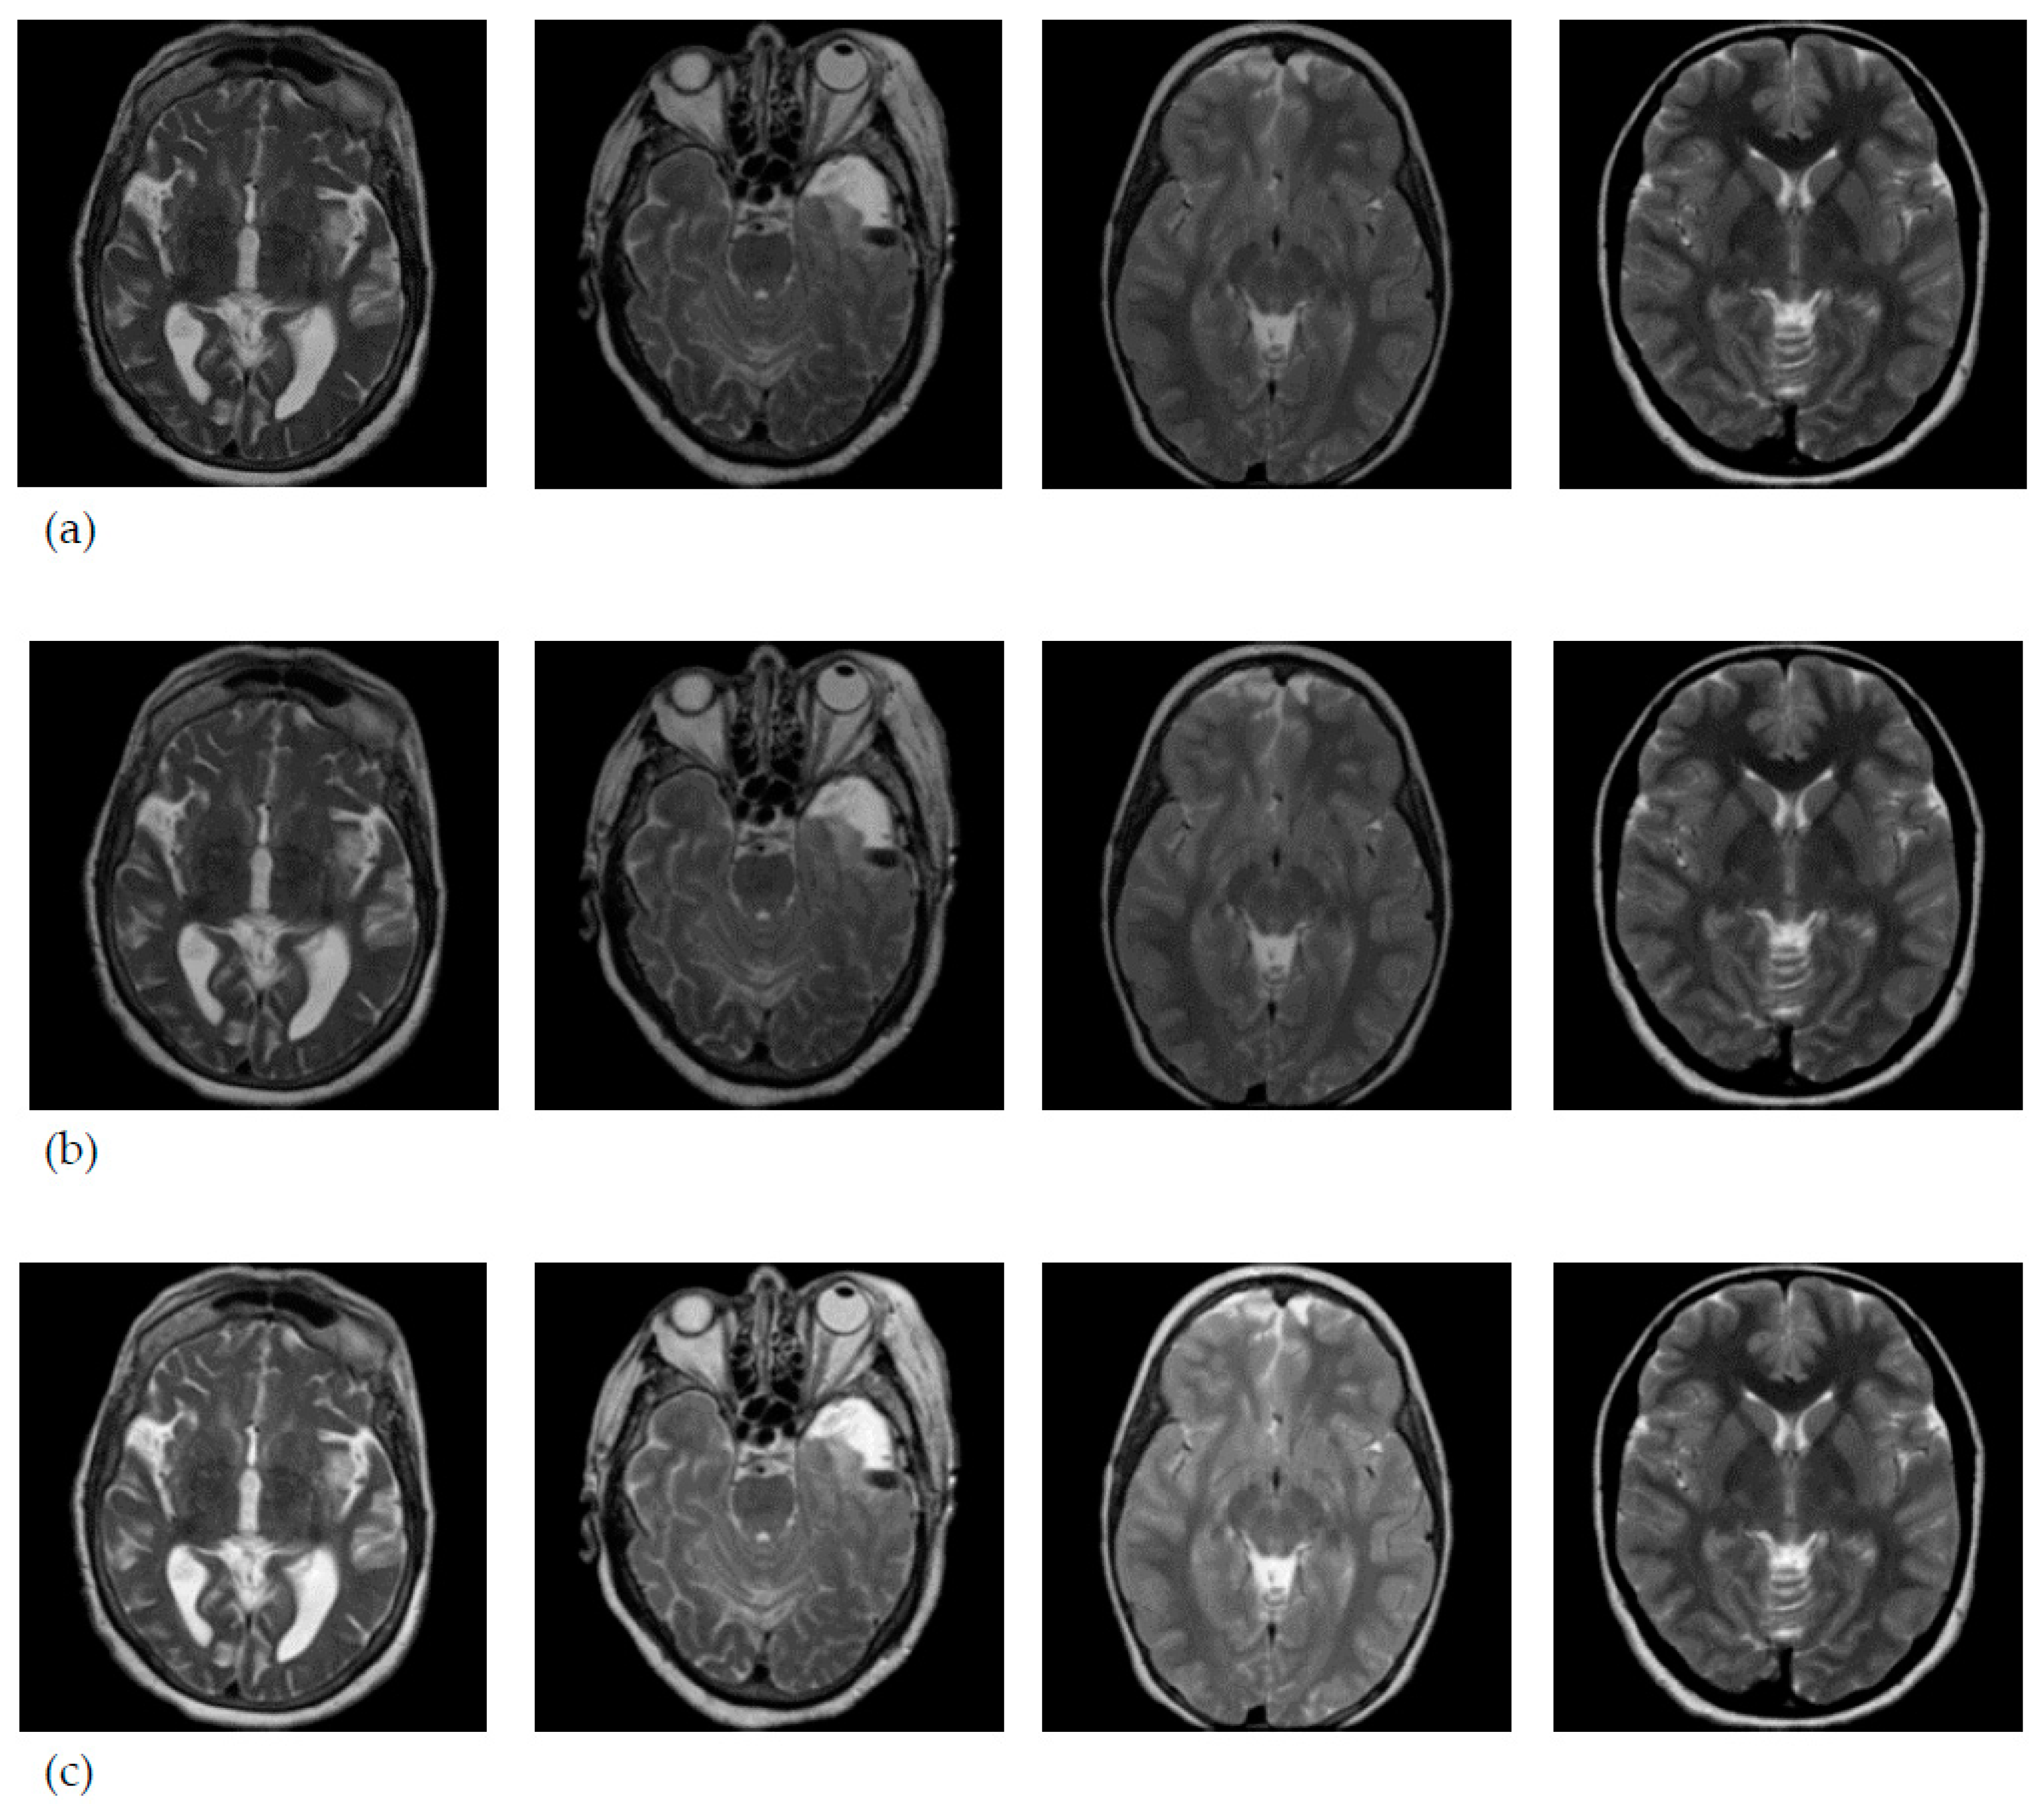

3.1. Data Collection

3.2. MRI Brain Scan Preprocessing